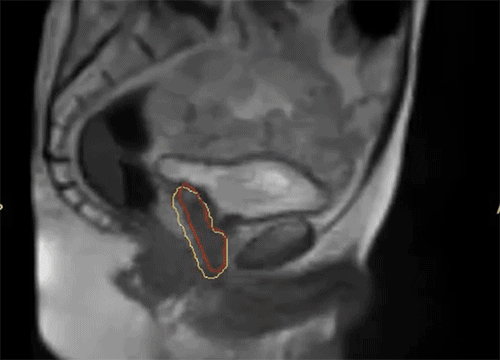

Dr. Camilleri表示,他们在做在线自适应放疗的时候,为了提高速度,仅对靶区外放3cm以内的危及器官的变化进行自适应调整或重新勾画轮廓,见Figure 13。这样可以缩短轮廓勾画的时间。对于放疗计划,使得95%的靶区体积接受到100%的处方剂量覆盖,并将最大剂量限制为2%的靶区体积不超过处方剂量的110%,这样就能保证在图像上很难显示的尿道不会超量,见Figure 14。另外,在制作放疗计划时,将PTV分为PTV LOW和PTV High,PTV和危及器官重叠的部分为PTV LOW,将PTV LOW的剂量目标设定在危及器官的耐受剂量以下,这样就能保证危及器官不超量,见Figure 15。

Dr. Camilleri表示前列腺放疗的分次间,前列腺的移动度不算大,但精囊腺的移动度较大,可以达到5mm左右,通过MRIdian每日在线自适应计划调整可以修正这些运动。

Figure 18 前列腺放疗的分次间,前列腺的移动度不算大,但精囊腺的移动度较大